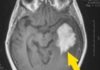

Les Tumeurs Cérébrales

ARTCLes Tumeurs Cérébrales